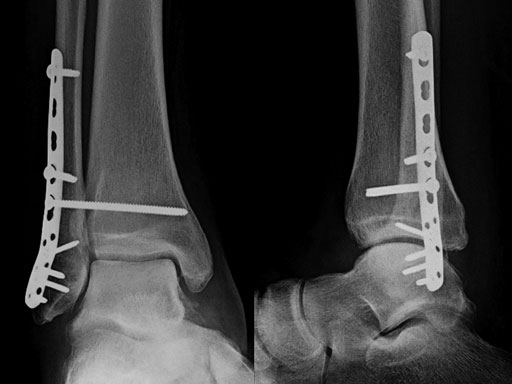

A 56-year-old man slipped and fell, sustaining a fracture dislocation of the ankle. His fibula was stabilized with a posterolateral plate. The construct included several nonlocking screws in the diaphysis, and multiple 2.7 mm locking screws in the distal fibula. As with most Weber B fracture patterns, a lag screw was possible from posterior to anterior through the plate. Finally, intraoperatively the patient was found to have a syndesmotic injury, and after reduction, a syndesmotic screw was placed through the plate.